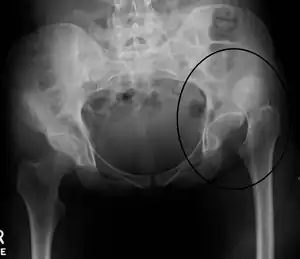

Uma luxação da anca (português europeu) ou luxação do quadril (português brasileiro) é uma deslocação da articulação entre o fémur e a bacia.[1] De forma mais específica, é quando a extremidade esférica do fémur se desencaixa do acetábulo da bacia onde está normalmente encaixada.[1] Os sintomas geralmente consistem em dor e incapacidade em mover a anca.[1] Entre as possíveis complicações estão a necrose avascular da anca, lesões no nervo ciático ou artrite.[1]

As luxações são geralmente causadas por traumatismos significativos, como os que resultam de acidentes de viação ou quedas de elevada altura.[1] Em muitos casos ocorrem também outras lesões associadas.[2][6] As luxações da anca podem também ser o resultado de uma substituição da anca ou de uma anomalia do desenvolvimento denominada displasia de desenvolvimento da anca.[7] O diagnóstico é geralmente confirmado com radiografias simples.[2]